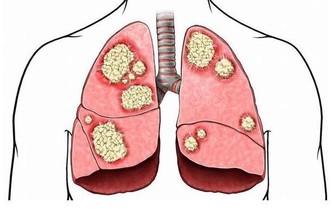

我們身上出現炎症很正常,手指割破了口子可能發炎,感冒了可能出現扁桃體發炎,吃壞了東西可能誘發急性腸炎……和這些器官組織一樣,關節也會發炎,出現關節炎。

這是一種影響所有年齡段人群的長期病症。最常見的類型是骨關節炎,由關節內光滑的軟骨逐漸磨損引起的。其症狀包括關節疼痛、壓痛、僵硬,並且在受影響的關節上皮膚會出現紅腫。